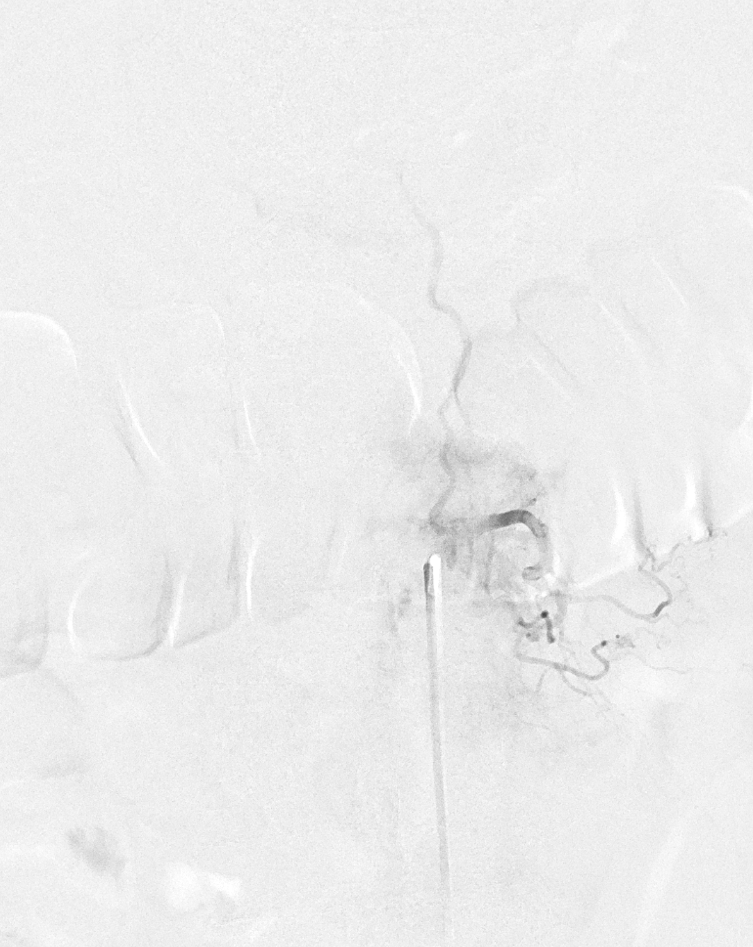

Post. It is important to control from other levels (left T12, left L2, and right L1) — not shown.

Key image here — injection of Adamkiewicz now shows return of the prodigal veins to the venous phase of the cord. Image on left also shows the now liberated basket.

pre and post Rx ASA views side by side

It is critical to understand cord venous drainage in post-dural fistula patients is never normal. The radicular veins are still missing. This may in part be responsible for the incomplete clinical recovery, although the main reason is probably cord damage before fistula occlusion.